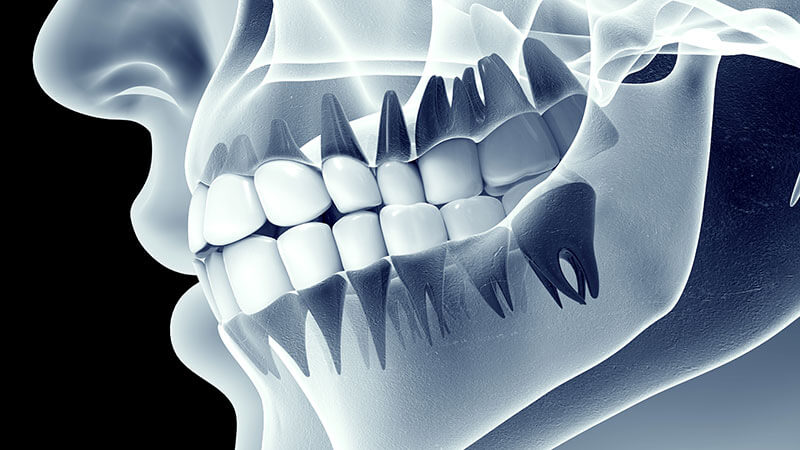

اکلوژن به معنای نحوه قرارگیری و تماس دندانهای فک بالا و پایین هنگام بستن دهان است. زمانی که این تماس به شکل صحیح و هماهنگ انجام شود، عملکرد جویدن، گفتار و حتی زیبایی لبخند در بهترین حالت خود قرار دارد. اما هرگونه اختلال در این هماهنگی، که به آن ناهنجاری اکلوژن یا مالاکلوژن گفته میشود، میتواند پیامدهای متعددی بر سلامت دهان و دندان و حتی ساختار صورت داشته باشد. تشخیص زودهنگام این ناهنجاریها در کودکان، فرصتی طلایی برای مداخلات ساده و پیشگیری از درمانهای پیچیده در آینده فراهم میکند. در این مقاله سایت دکتر ندا مکانیک بهترین دندانپزشک کودکان اصفهان، تشخیص زودهنگام ناهنجاریهای اکلوژن و مداخلات ساده را مورد بررسی قرار خواهیم داد.

ناهنجاری اکلوژن چیست؟

ناهنجاری اکلوژن به هرگونه عدم هماهنگی در قرارگیری دندانها یا فکها گفته میشود. این مشکل میتواند شامل:

- شلوغی یا فاصله بین دندانها

- جلو زدگی یا عقبرفتگی فکها

- بایت باز یا بایت عمیق

- انحراف خط میانی دندانها